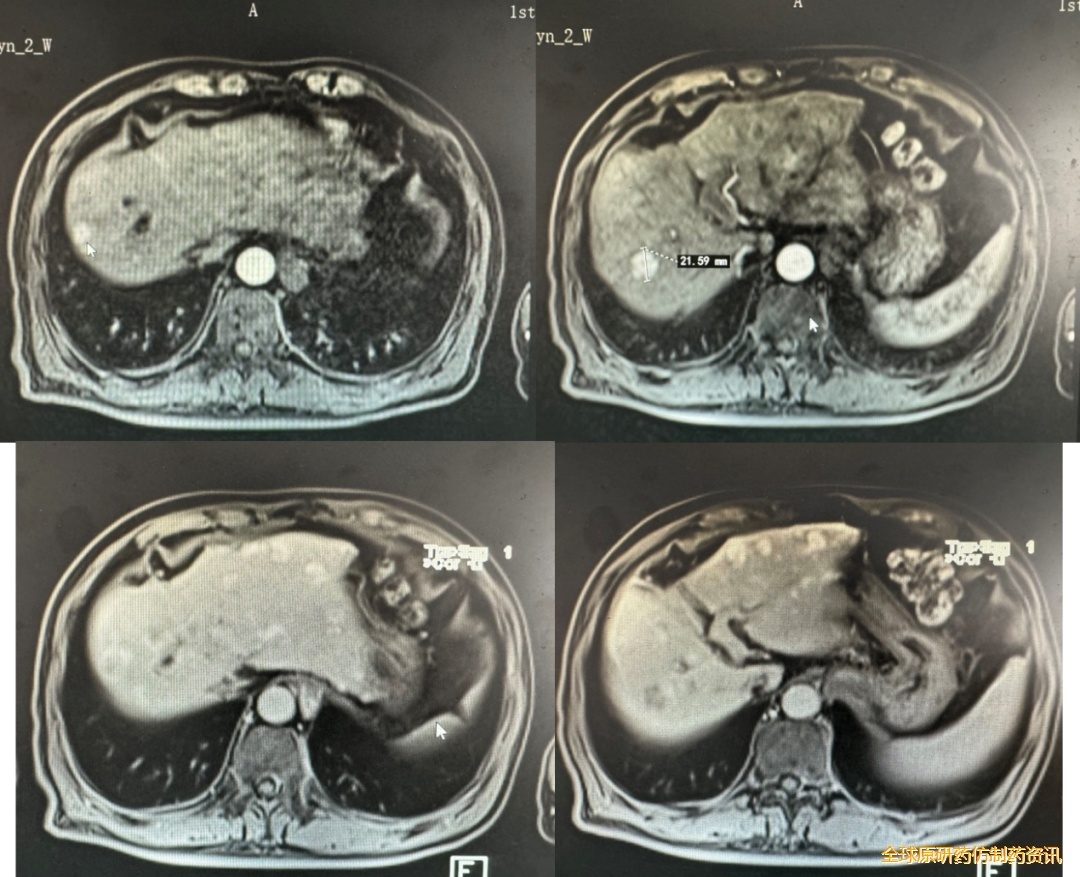

术后病理:肝脏符合肝细胞肝癌伴广泛坏死,中分化,断端净。

免疫组化结果:CK (+),CK7(-),Hepa(+),Glypican-3弱(+),CK8(+),CD34(+),CD10(-),Ki67(5%+),P63(-),HSP70(+),GS(+)。

图3 病理图片